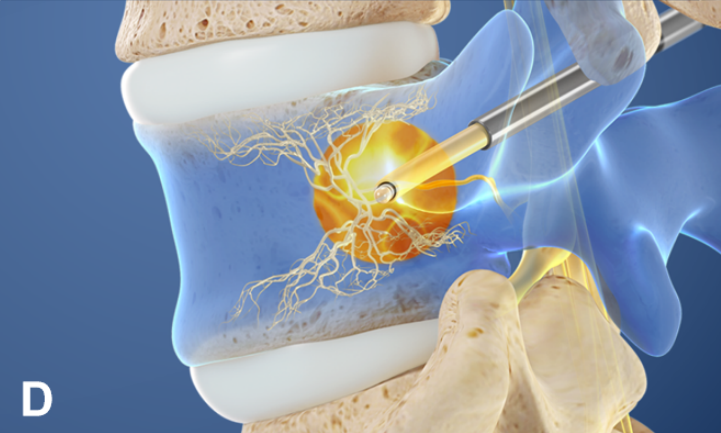

②椎体内椎基神经射频消融术

值得关注的是,系列前瞻性多中心随机对照研究和前瞻性观察研究证实椎体内椎基神经射频消融术可有效缓解疼痛性 Ⅰ 型或 Ⅱ 型 Modic 改变患者的腰痛症状,减少阿片类药物的用量,且疗效优于保守治疗。

国际脊柱外科手术学会指南也推荐采用椎体内椎基神经射频消融术治疗 Ⅰ 型或 Ⅱ 型 Modic 改变引起的慢性腰痛。

2021 年,Conger 等进行系统综述发现有中等质量的证据表明,在根据存在 Ⅰ 型或 Ⅱ 型 Modic 改变选择慢性腰痛患者时,椎体内椎基神经射频消融术可有效改善慢性腰痛患者的疼痛和功能障碍。这可能与灭活了椎体内的椎基神经, 阻断了神经传导通路有关。